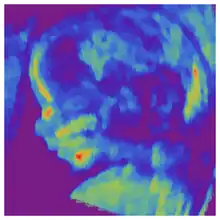

Biparietal diameter is taken as the maximal transverse diameter of in a visualization of the horizontal plane of the head.

Biparietal diameter (the transverse diameter of the head) by gestational age, with the blue line representing the mean and the green area representing the 90% prediction interval.[14]

Gestational age is usually determined by the date of the woman's last menstrual period, and assuming ovulation occurred on day fourteen of the menstrual cycle. Sometimes a woman may be uncertain of the date of her last menstrual period, or there may be reason to suspect ovulation occurred significantly earlier or later than the fourteenth day of her cycle. Ultrasound scans offer an alternative method of estimating gestational age. The most accurate measurement for dating is the crown-rump length of the fetus, which can be done between 7 and 13 weeks of gestation. After 13 weeks of gestation, the fetal age may be estimated using the biparietal diameter (the transverse diameter of the head, across the two parietal bones), the head circumference, the length of the femur, the crown-heel length (head to heel), and other fetal parameters. Dating is more accurate when done earlier in the pregnancy; if a later scan gives a different estimate of gestational age, the estimated age is not normally changed but rather it is assumed the fetus is not growing at the expected rate.[5]